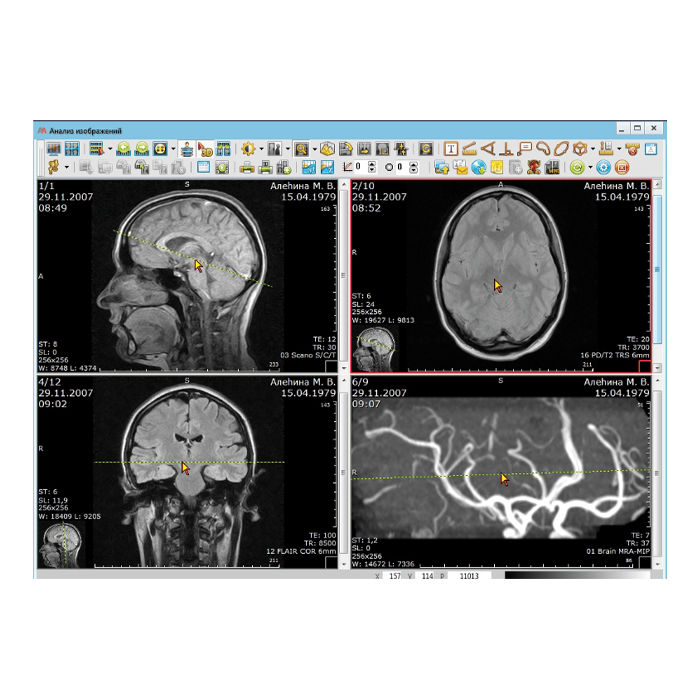

АрхиМед PACS/RIS — это комплексное программное решение для цифровизации и оптимизации работы лучевой диагностики. Система объединяет процессы управления исследованиями (RIS), хранения и обработки медицинских изображений (PACS), а также создания структурированных отчетов. Это фундамент для создания современного, эффективного и безопасного радиологического отделения или целой сети медицинских учреждений.

- Работа с изображениями: Автоматический прием снимков с любого DICOM-совместимого оборудования (КТ, МРТ, рентген, УЗИ и др.), организация единого защищенного архива.

- Описание и отчетность: Удобные рабочие станции для врачей-рентгенологов с шаблонами протоколов, голосовым вводом и поддержкой нормативных форм.

- Повышение качества диагностики: Доступ к полной истории изображений пациента, инструменты для сравнения, точных измерений и постобработки.